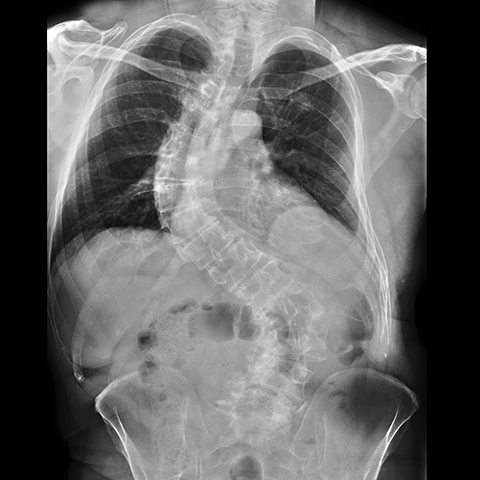

12 year old girl with back pain